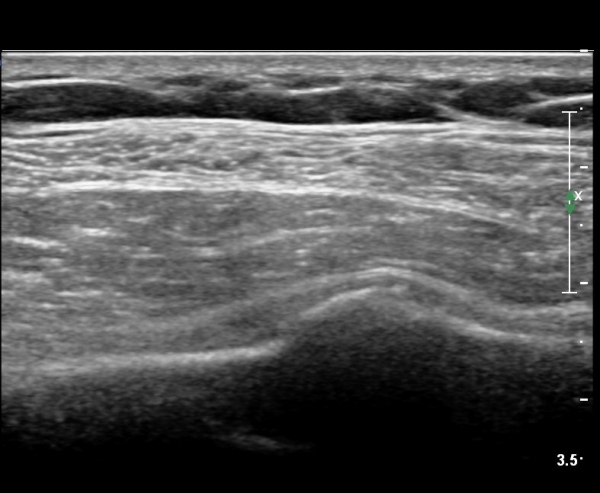

lin longitudinal scan of 7th. rib, appearance of bony mass(protrusion) just like callus(image 1).

on moving of prove a little, there is bony protrusion(osteoblastic lesion) and hypoechoic(osteolytic)  lesion(image 2, 3, 4).